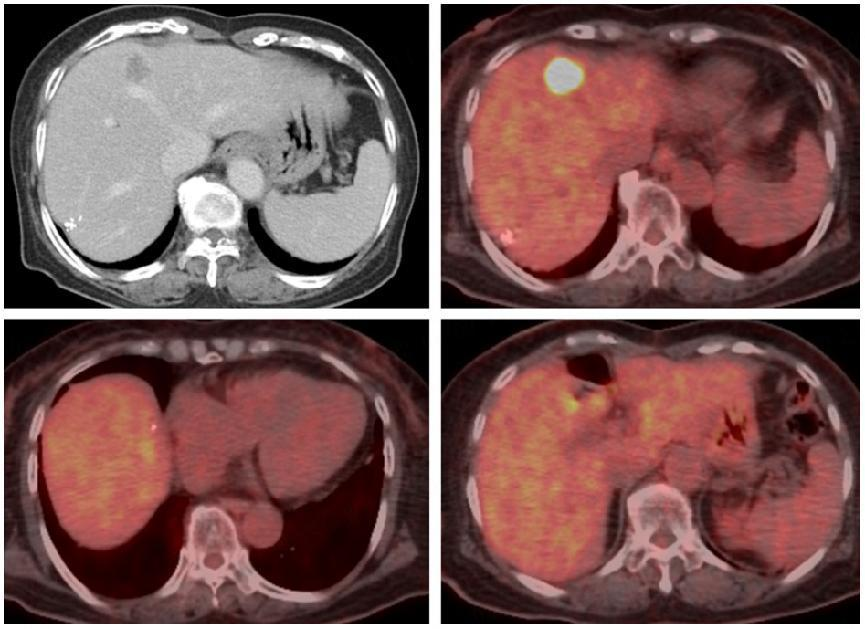

食管胃十二指肠镜检查(EGD):BORRmann II型肿瘤占据胃窦弯侧(图1a)。

增强CT:提示多发性肝、淋巴结转移(图1b,图2a、b)。

全身FDG-PET:原发部位胃以及7个肝转移灶代谢增高(图1c,图2c、d)。

病理学检查:(胃窦肿物)中分化腺癌,HER2免疫组化评分为3+(图1d)。

图1:初诊时内镜、影像学和病理学检查(a,EGD;b,增强CT;c,FDG-PET;d,病理学检查)